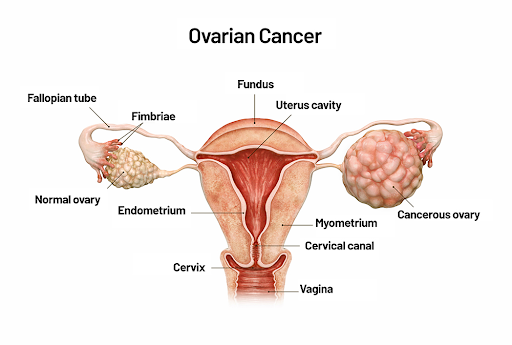

What is Ovarian Cancer?

Ovarian cancer is a type of cancer that develops in or near the ovaries, which are part of the female reproductive system. The ovaries produce eggs and hormones, including estrogen and progesterone. Ovarian cancer occurs when cells in this area grow and divide in an uncontrolled way.

2. Where It Begins +

Which part of the body is involved?

Ovarian cancer involves the ovaries, two small organs located on either side of the uterus in the lower abdomen. In some cases, the cancer may begin in nearby tissues, such as the surface lining of the ovary or the cells of the fallopian tubes, but it is still categorized as ovarian cancer.

The ovaries play a key role in reproduction and hormone regulation.